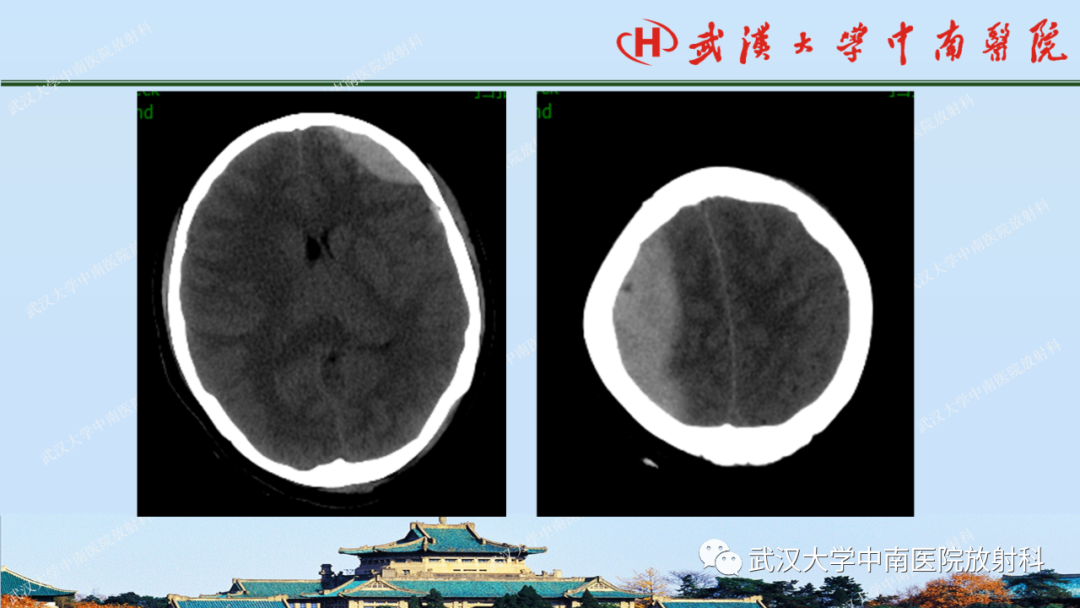

【PPT】脑外伤影像学诊断